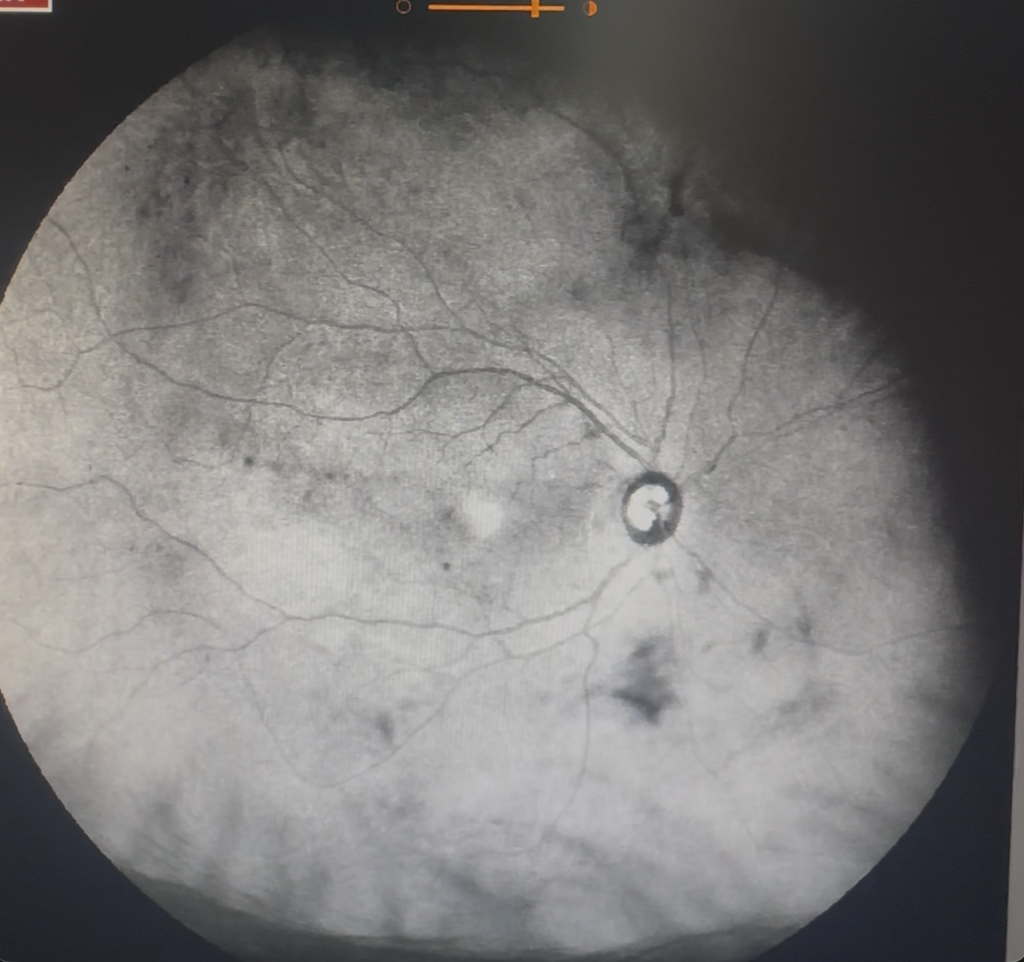

Diagnóstico y tratamiento de padecimientos que afectan la parte del ojo responsable

de la visión, como retinopatía diabética…

Tecnología avanzada para evaluar la retina y estructuras oculares, permitiendo detectar enfermedades.

Procedimiento especializado que permite tratar enfermedades que afectan la parte del ojo responsable de la visión.